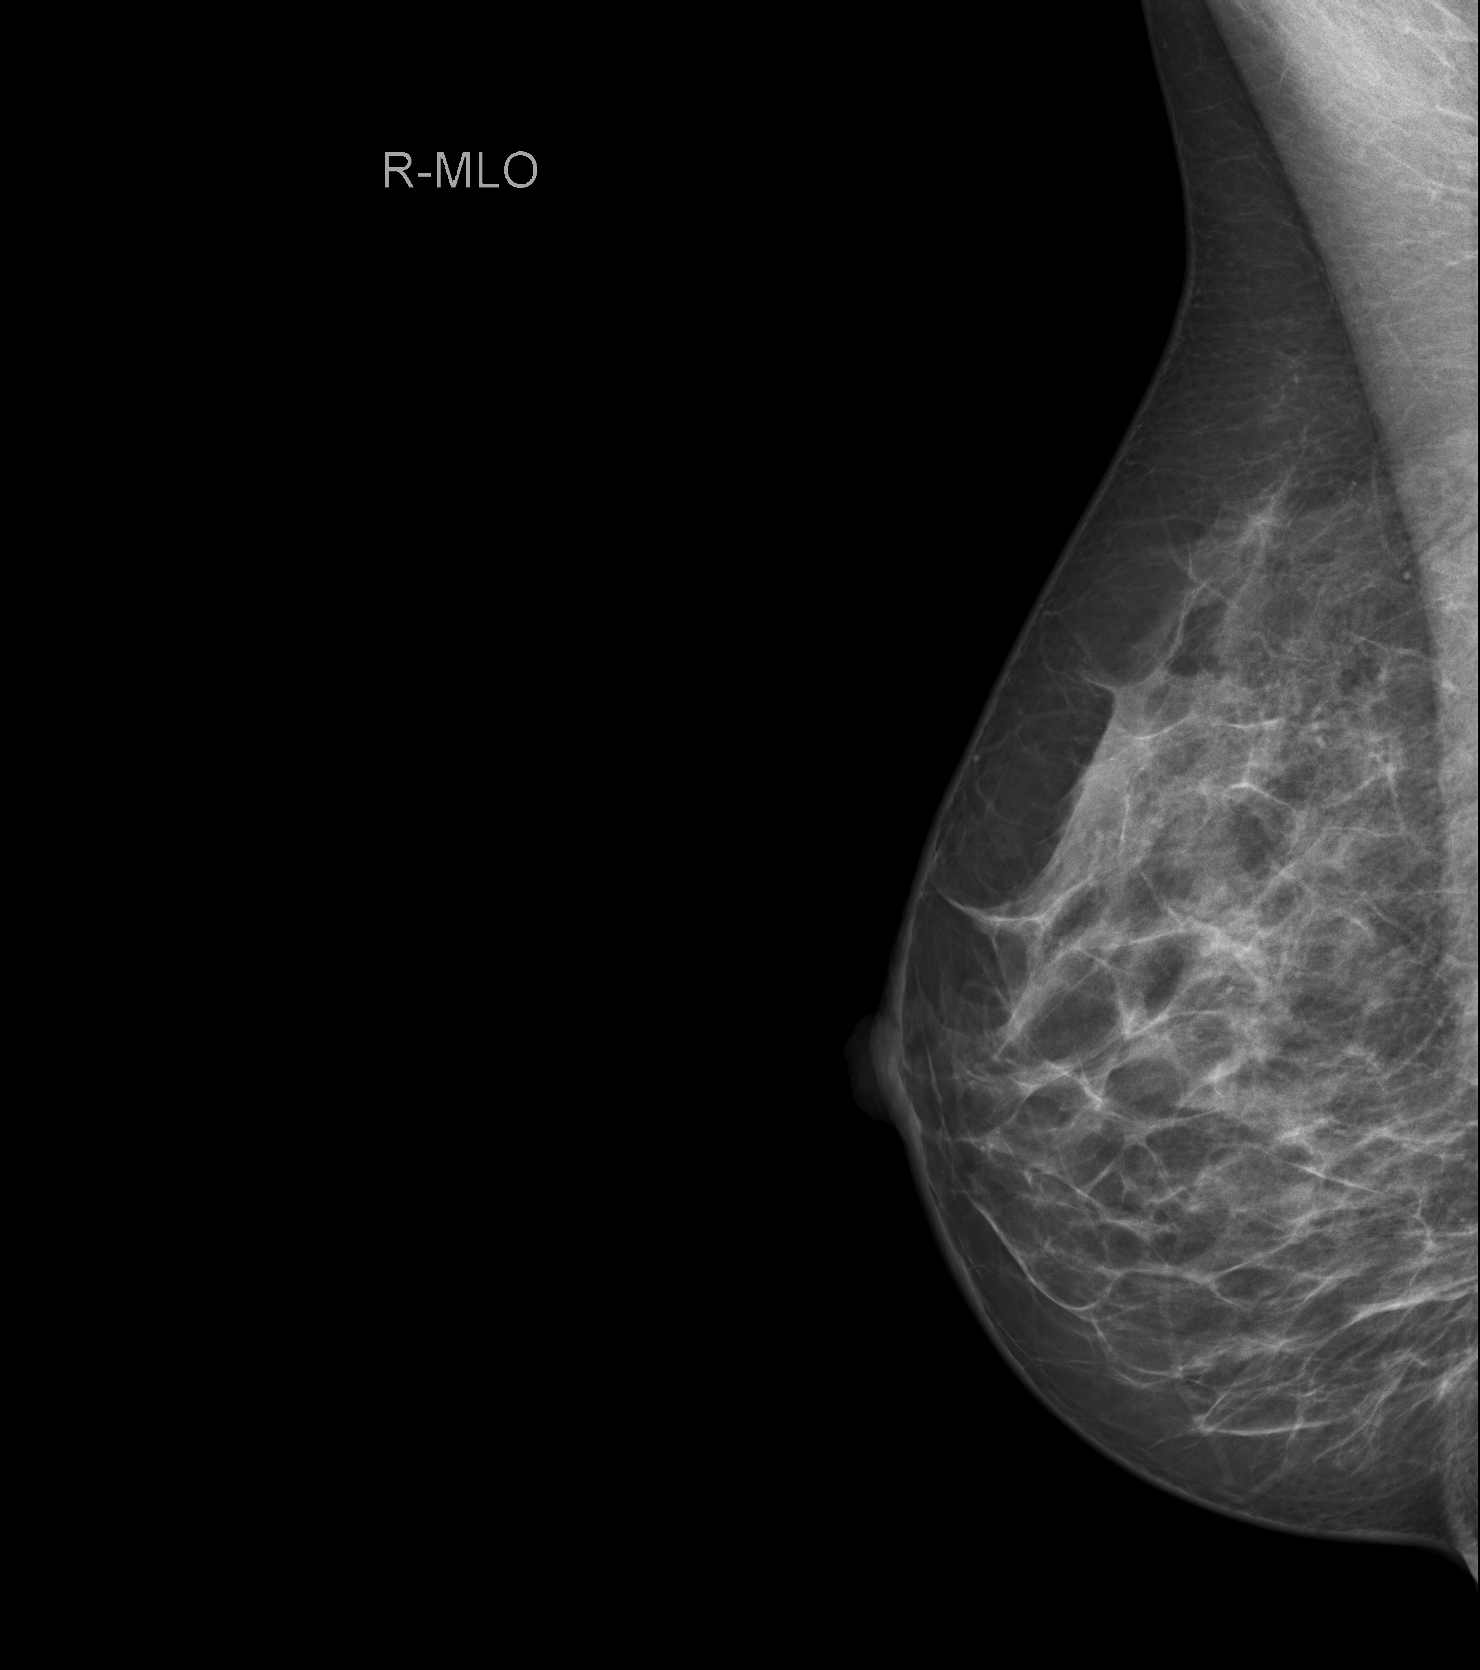

Die Mammographie ist eine Röntgenuntersuchung der Brust. Sie wird mit einem digitalen Vollfeldsystem durchgeführt. Die Untersuchung wird im Rahmen des Brustkrebsfrüherkennungsprogramms bei Frauen ab dem vierzigsten Lebensjahr empfohlen. Auch bei Beschwerden oder familiärer Vorbelastung wird je nach Anamnese eine Mammographie durchgeführt.

Das neue Mammographiesystem „Mammomat Revelation“ der Firma Siemens Healthineers, mit dem einzigartigen Tomosyntheseverfahren, ermöglicht uns eine höhere Entdeckungsrate von Brustkrebs bei geringerer Strahlendosis. Bei der Mammographie werden von jeder Brust zwei Aufnahmen in verschiedenen Ebenen angefertigt. Die Brust wird dabei leicht dosiert komprimiert, um eine optimale Bildqualität bei geringster Strahlenbelastung zu erreichen. Zusätzlich besteht die Möglichkeit einer Tomosynthese, die überwiegend bei dichtem Drüsengewebe eingesetzt wird. Diese neue Technologie ermöglicht uns eine Schichtbildaufnahme der Brust, wodurch ein 3D-Eindruck entsteht und somit wird die Diagnosegenauigkeit erhöht.